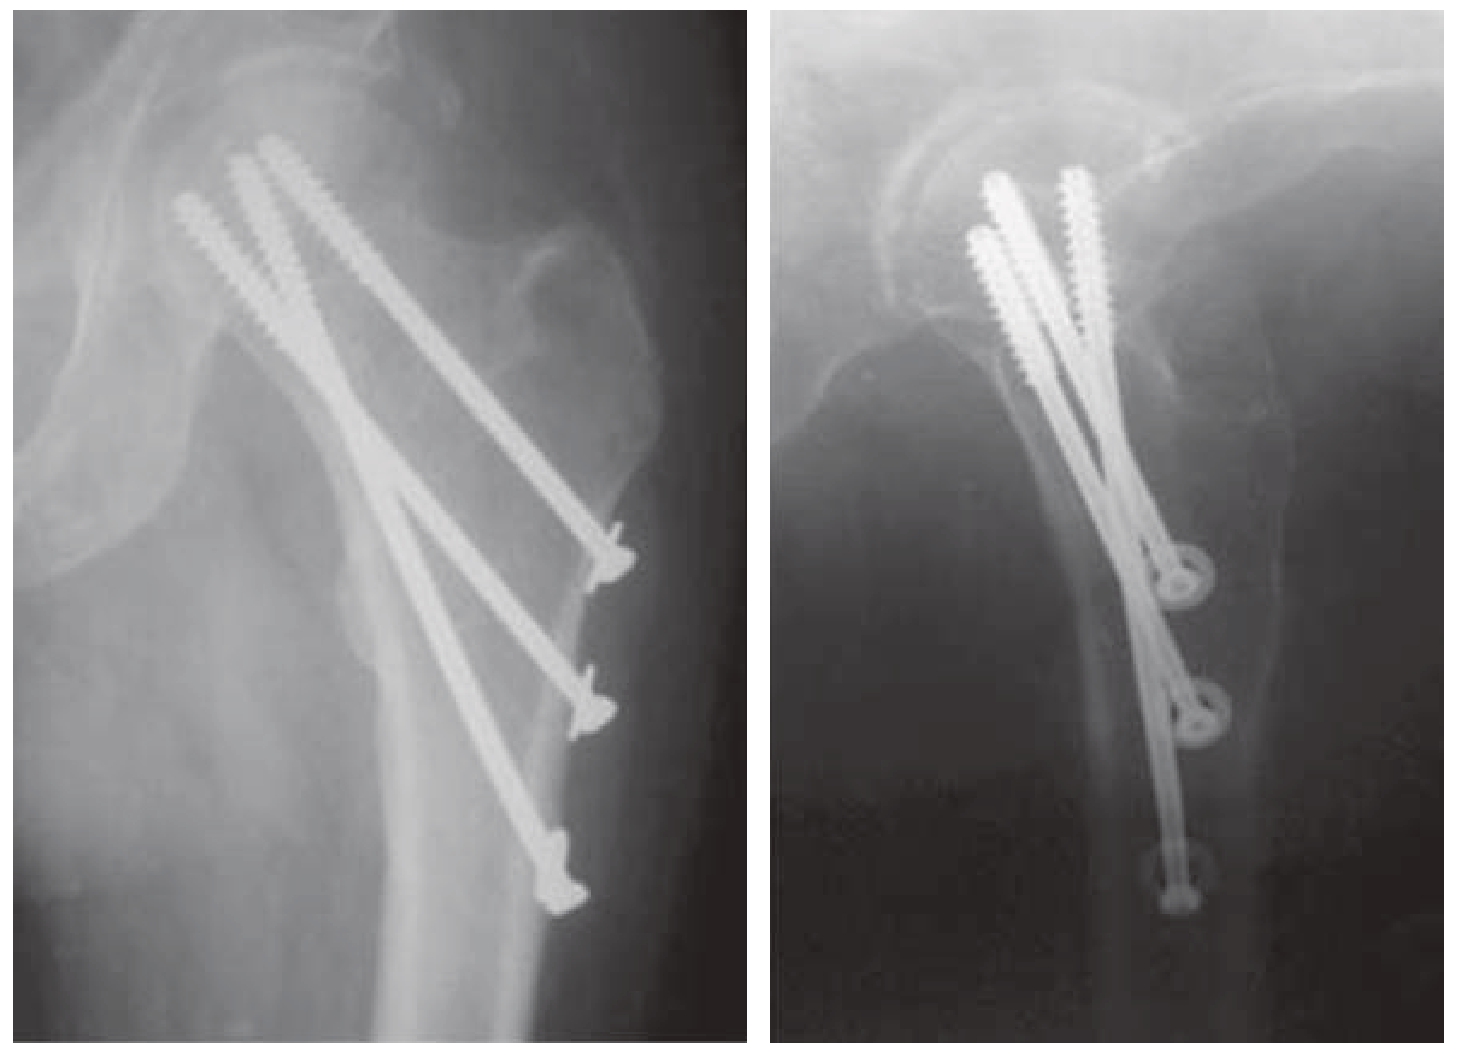

2)F构型螺钉固定:偏轴螺钉固定中还有一种比较特殊的方法,即F构型螺钉固定。F型固定最初是在2011年由保加利亚医生Filipov O提出的,他提出双平面双支撑螺钉固定(biplane double-supported screw fixation,BDSF)技术。3枚空心拉力螺钉植入股骨颈后,在髋关节前后位X线影像上呈字母F形,2枚螺钉沿股骨颈轴向纵行植入,其中一枚贴股骨颈远侧皮质植入(第二枚);另一枚螺钉以低位进针点,一般低于小转子下缘水平向股骨头内、贴股骨颈远侧皮质植入,与第二枚螺钉交叉(第三枚)(图9—5)。因此在冠状面上形成双支撑点,即内侧支撑点在股骨颈远侧皮质(股骨距处),有第二和第三枚螺钉于皮质处交叉形成支撑(交叉支撑)及外侧支撑点,3枚螺钉在股骨干外侧皮质的螺钉进钉点分散形成(分散支撑)。在髋关节侧位X线片上,前两枚螺钉于颈的前侧向头前部植入,第三枚螺钉于颈的后侧向后植入,在后侧皮质处形成支撑。Filipov提出F型固定的适应证是Garden Ⅰ~Ⅳ型骨折,并进行了一系列的研究报道。2011年最初的临床研究为病例系列研究[22],共88例股骨颈骨折患者接受了F型固定,平均年龄76.9岁(38~99岁),Garden Ⅰ型3例(3.41%)、Garden Ⅱ型1例(1.14%)、Garden Ⅲ型9例(10.23%)、Garden Ⅳ型75例(85.02%),经过短期平均8.06个月的随访,骨折愈合率达到98.86%,平均HHS评分84.26,优良率达到65.90%。2015年,Filipov对BDSF固定进行了生物力学研究[23]。通过尸体骨模型模拟了AO/OTA31—B2.2型股骨颈骨折,比较了传统的倒三角构型PLCS和BDSF,通过静态和动态实验发现与常规固定相比,力学情况越不稳定,BDSF的稳定性越好。BDSF在各种生理载荷中维持持续稳定。在垂直压缩载荷情况(模拟站立位)下,股骨距皮质支撑螺钉增强了支撑和角稳定性,近端螺钉提供了抗张力;在前后弯曲载荷(模拟坐姿起立)下,远端螺钉后侧皮质支撑抵抗了前后向移位,另两枚前方的螺钉提供了抗张力。2017年,Filipov再次报道了更大样本量的病例系列研究[24],该研究共纳入207例骨折,平均年龄76岁(38~99岁),其中Garden Ⅲ型15例(5.2%)、Garden Ⅳ型192例(92.8%),经过平均29.6个月的随访,骨折愈合率仍高达96.6%,不愈合率仅3.4%,股骨头坏死率为12.1%,平均HHS评分86.2。由于F型固定理念创新,其已经得到不少的关注,甚至《美国骨科医师协会杂志》(Journal of The American Academy of Orthopaedic Sur geons,JAAOS)在2019年专门对BDSF的技术细节进行了专刊报道[25],但目前报道的临床结果还是令人震惊和值得深思。按照目前形成的共识,一般对超过65岁的老年股骨颈骨折患者而言内固定并不是首选,而且内固定后骨折不愈合、股骨头坏死等并发症率一直影响着该年龄人群的最终结局。老年患者的骨质疏松问题也会影响内固定的稳定性,内固定失败率必然不低。高龄患者往往无法接受再次手术。此外,BDSF固定的另一隐患是医源性转子下骨折风险,这也是应用BDSF技术时不得不考虑的一个问题。到目前为止还没有BDSF针对性应用于垂直型股骨颈骨折相关研究的报道。

img

图9—5 F构型螺钉固定病例